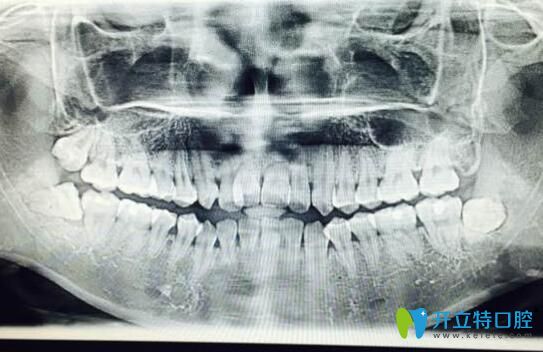

案例一:90后自述門牙牙根短做矯正感受:

首先我的門牙牙根很短,兩個醫(yī)生拒絕給我矯正的,但是我整牙欲望很強(qiáng)烈,冒著風(fēng)險做了,也不知道以后會出現(xiàn)什么問題,門牙是否真的掉了,到時候再說吧,問題出了再去解決…

90后自述門牙牙根短做矯正感受

?牙齒矯正2個月:?感覺牙齒變化速度比較慢,目前牙齒還沒又松動神馬的感覺。

牙根短做矯正效果